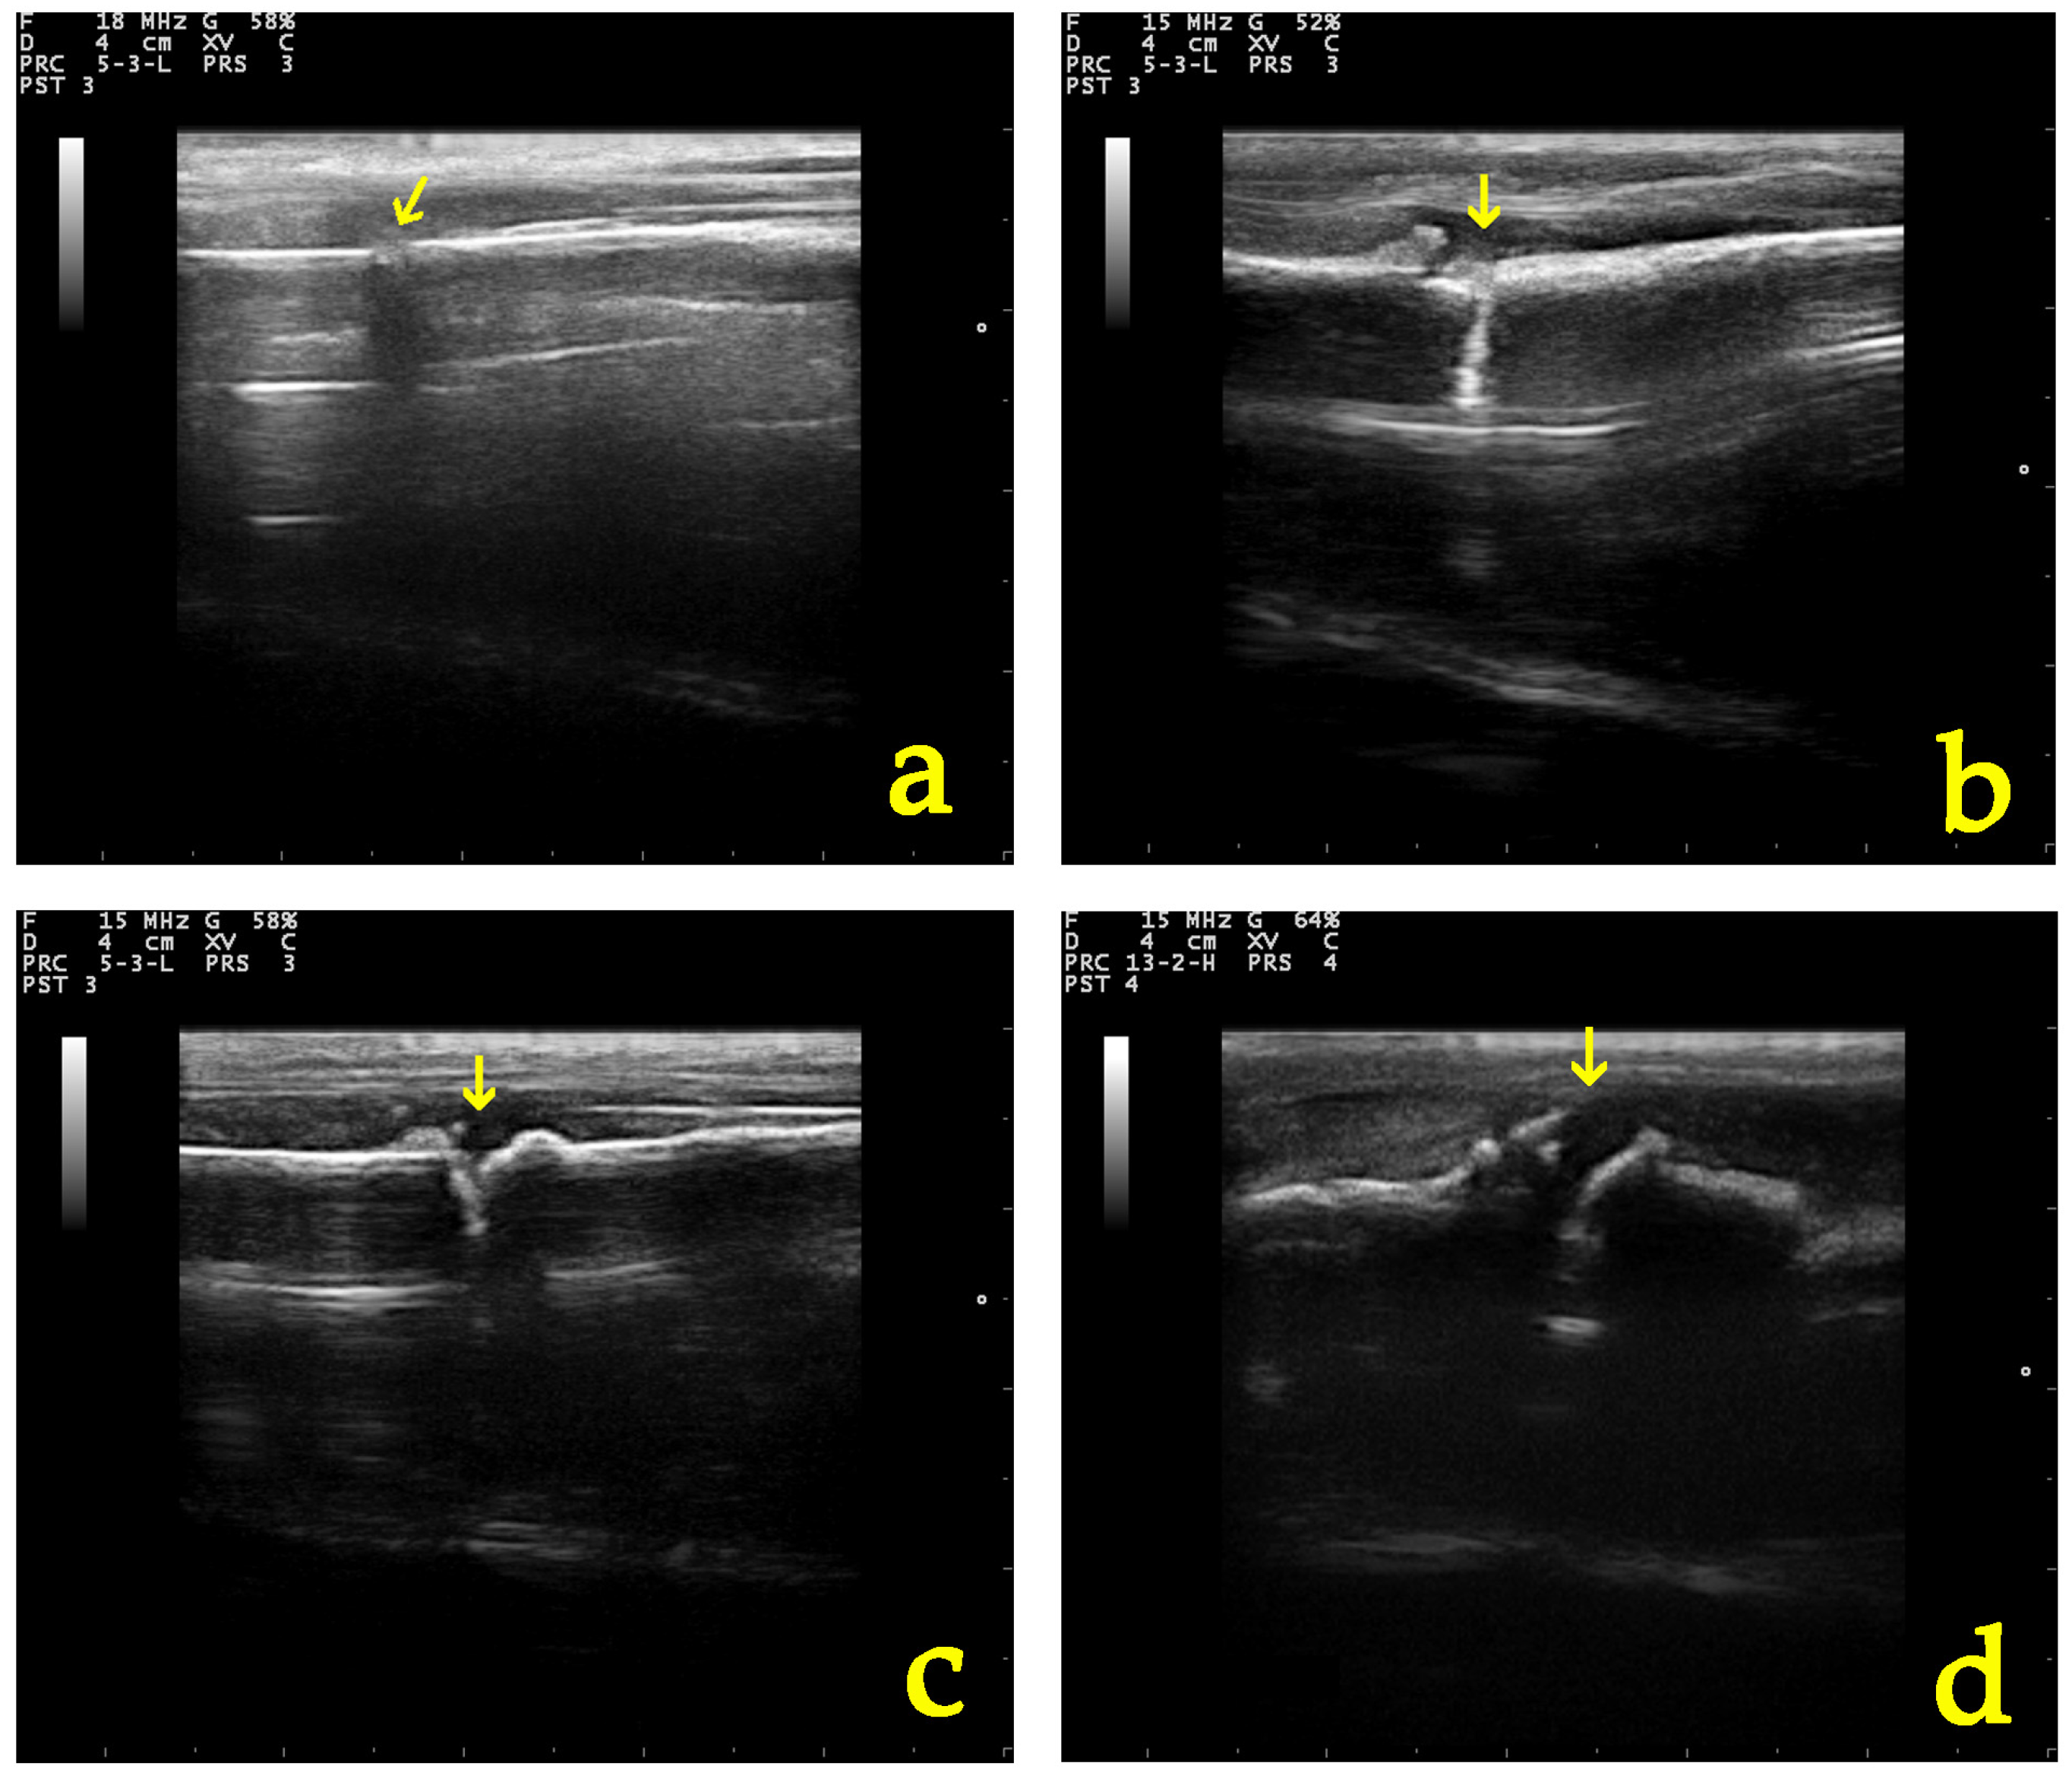

3.5.1. Ultrasonographic Examination

3.5.2. Radiographic Examination

| Parameter of Ultrasonographic Examination | Group | D0 | D5 | D10 | D20 | D28 |

|---|---|---|---|---|---|---|

| Echogenicity and structural organization of the tissue at the fracture site | A | 1 (1–1) | 2 (1–2) | 2 (2–2) | 3 (3–4) | 3.5 (3–4) |

| B | 1 (1–1) | 1 (1–2) | 2 (2–2) | 3 (2–4) | 4 (2–4) | |

| Formation of the callus and the vascularization present at the osteotomy | A | 1 (1–1) | 2 (2–2) | 2 (2–2) | 3 (2–4) | 3.5 (3–4) |

| B | 1 (1–1) | 2 (2–2) | 2 (1–2) | 3 (2–4) | 4 (2–4) | |

| Total grade | A | 1 (1–1) | 1.5 (1–2) | 2 (2–2) | 3 (3–4) | 3.5 (3–4) |

| B | 1 (1–1) | 1 (1–2) | 2 (2–2) | 3 (2–4) | 4 (2–4) |